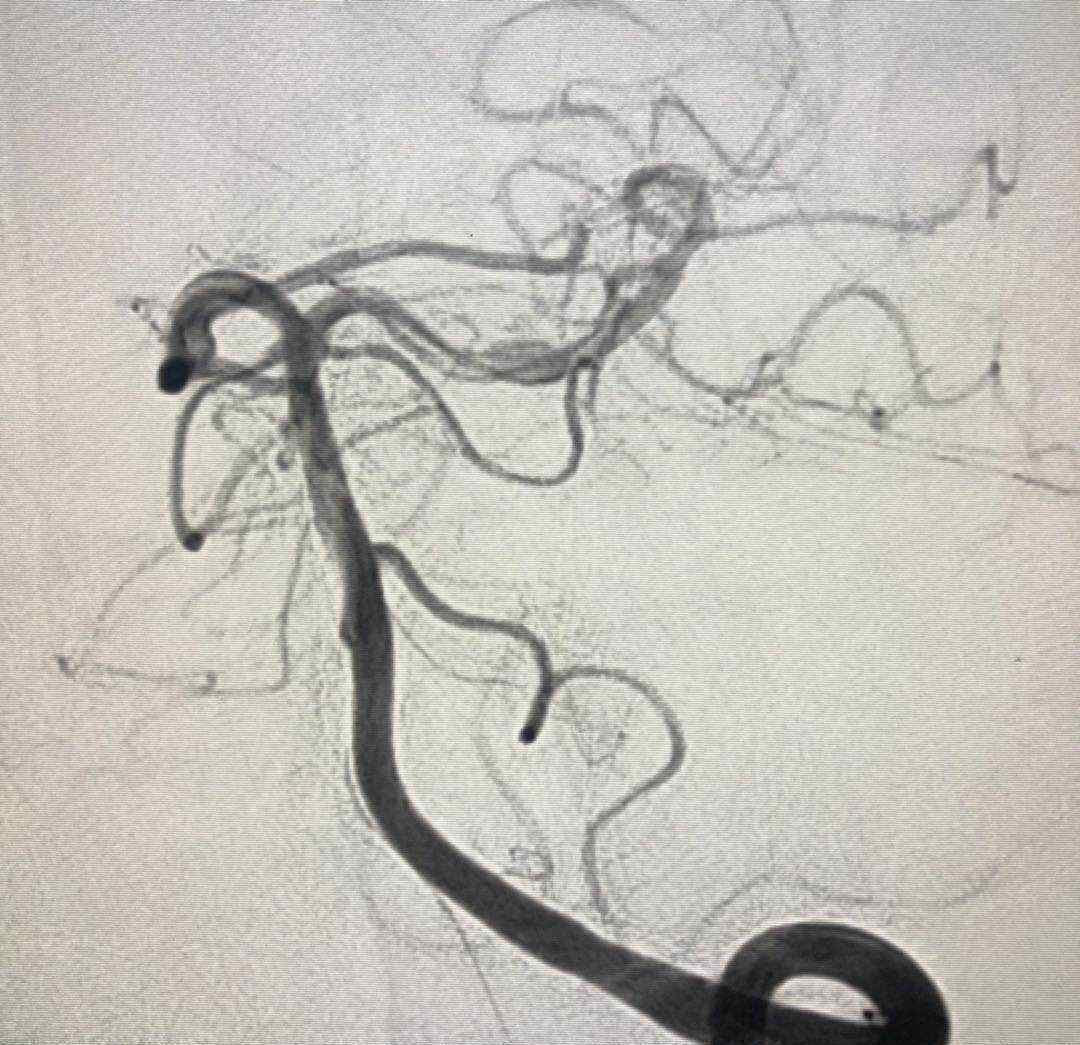

入院后行CTA,考虑左侧后交通动脉瘤。但局部高密度影,考虑动脉瘤破裂出血或巨大动脉瘤附壁血栓可能性大。

考虑为宽基底4.9毫米,大小约为7.9*7.1毫米。

于2019.4.18日行颅内动脉瘤栓塞术